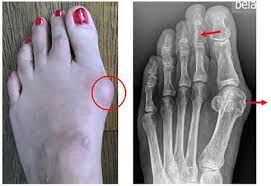

Zuvor wird aber versucht dass Überbein mit anderen Mitteln zu entfernen. Am Mittelfußknochen stehen sie meistens in Zusammenhang mit Hallux ridigus einer durch Arthrose verursachten Veränderung des Zehengelenks.

Insofern können Fußrücken und Ferse aber auch Handgelenk oder Knie davon betroffen sein. Die operative Entfernung eines Überbeines besteht meistens darin dieses mithilfe einer Hohlnadel zu punktieren und die Flüssigkeit ablaufen zu lassen. Welche Ursachen dahinterstecken und was Sie bei einem Überbein tun können erfahren Sie im Folgenden. Greift ein Arzt zur Nadel sind die. Das Überbein oder Ganglion ist eine gutartige Geschwulst die vereinzelt oder mehrfach im Bereich einer Gelenkkapsel auftritt. Vor allen Dingen wenn ein Überbein sehr groß ist können die Nervenfasern abgedrückt werden. Überbeinbehandlungen haben normalerweise einen gutartigen Verlauf dies ändert sich auch durch eine eventuelle Wiederkehr der Geschwulst nicht. Als Ganglion oder Überbein bezeichnet man eine Gelenkkapsel oder eine Sehnenscheide die aussackt. Mit einer Exostose am Fuß wird das Tragen von Schuhen langfristig schwierig und mitunter sehr schmerzhaft.